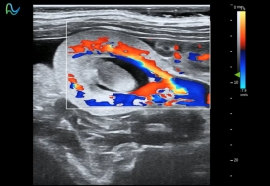

高频超声成像